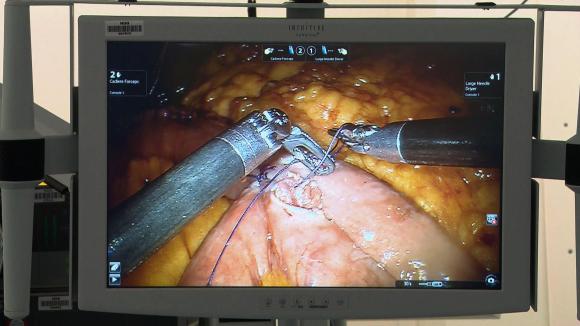

En el futuro, el uso de estos sistemas de cirugía robótica podría formar parte de la formación de los estudiantes de Medicina. AFP

Morel controla los numerosos brazos del robot desde el otro lado de la sala de operación, al efectuar microincisiones en los tejidos de un paciente. El sistema robotizado es utilizado principalmente para las intervenciones ginecológicas, de la próstata y en las histerectomías.